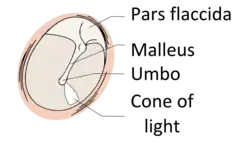

The eardrum is divided into two general regions: the pars flaccida and the pars tensa.[3] The relatively fragile pars flaccida lies above the lateral process of the malleus between the Notch of Rivinus and the anterior and posterior malleal folds. Consisting of two layers and appearing slightly pinkish in hue, it is associated with Eustachian tube dysfunction and cholesteatomas.[4]

The larger pars tensa consists of three layers: skin, fibrous tissue, and mucosa. Its thick periphery forms a fibrocartilaginous ring called the annulus tympanicus or Gerlach's ligament.[5] while the central umbo tents inward at the level of the tip of malleus. The middle fibrous layer, containing radial, circular, and parabolic fibers, encloses the handle of malleus. Though comparatively robust, the pars tensa is the region more commonly associated with perforations.[6]

The manubrium (Latin for "handle") of the malleus is firmly attached to the medial surface of the membrane as far as its center, drawing it toward the tympanic cavity. The lateral surface of the membrane is thus concave. The most depressed aspect of this concavity is termed the umbo (Latin for "shield boss").[7]

When the eardrum is illuminated during a medical examination, a cone of light radiates from the tip of the malleus to the periphery in the anteroinferior quadrant, this is what is known clinically as 5 o'clock.